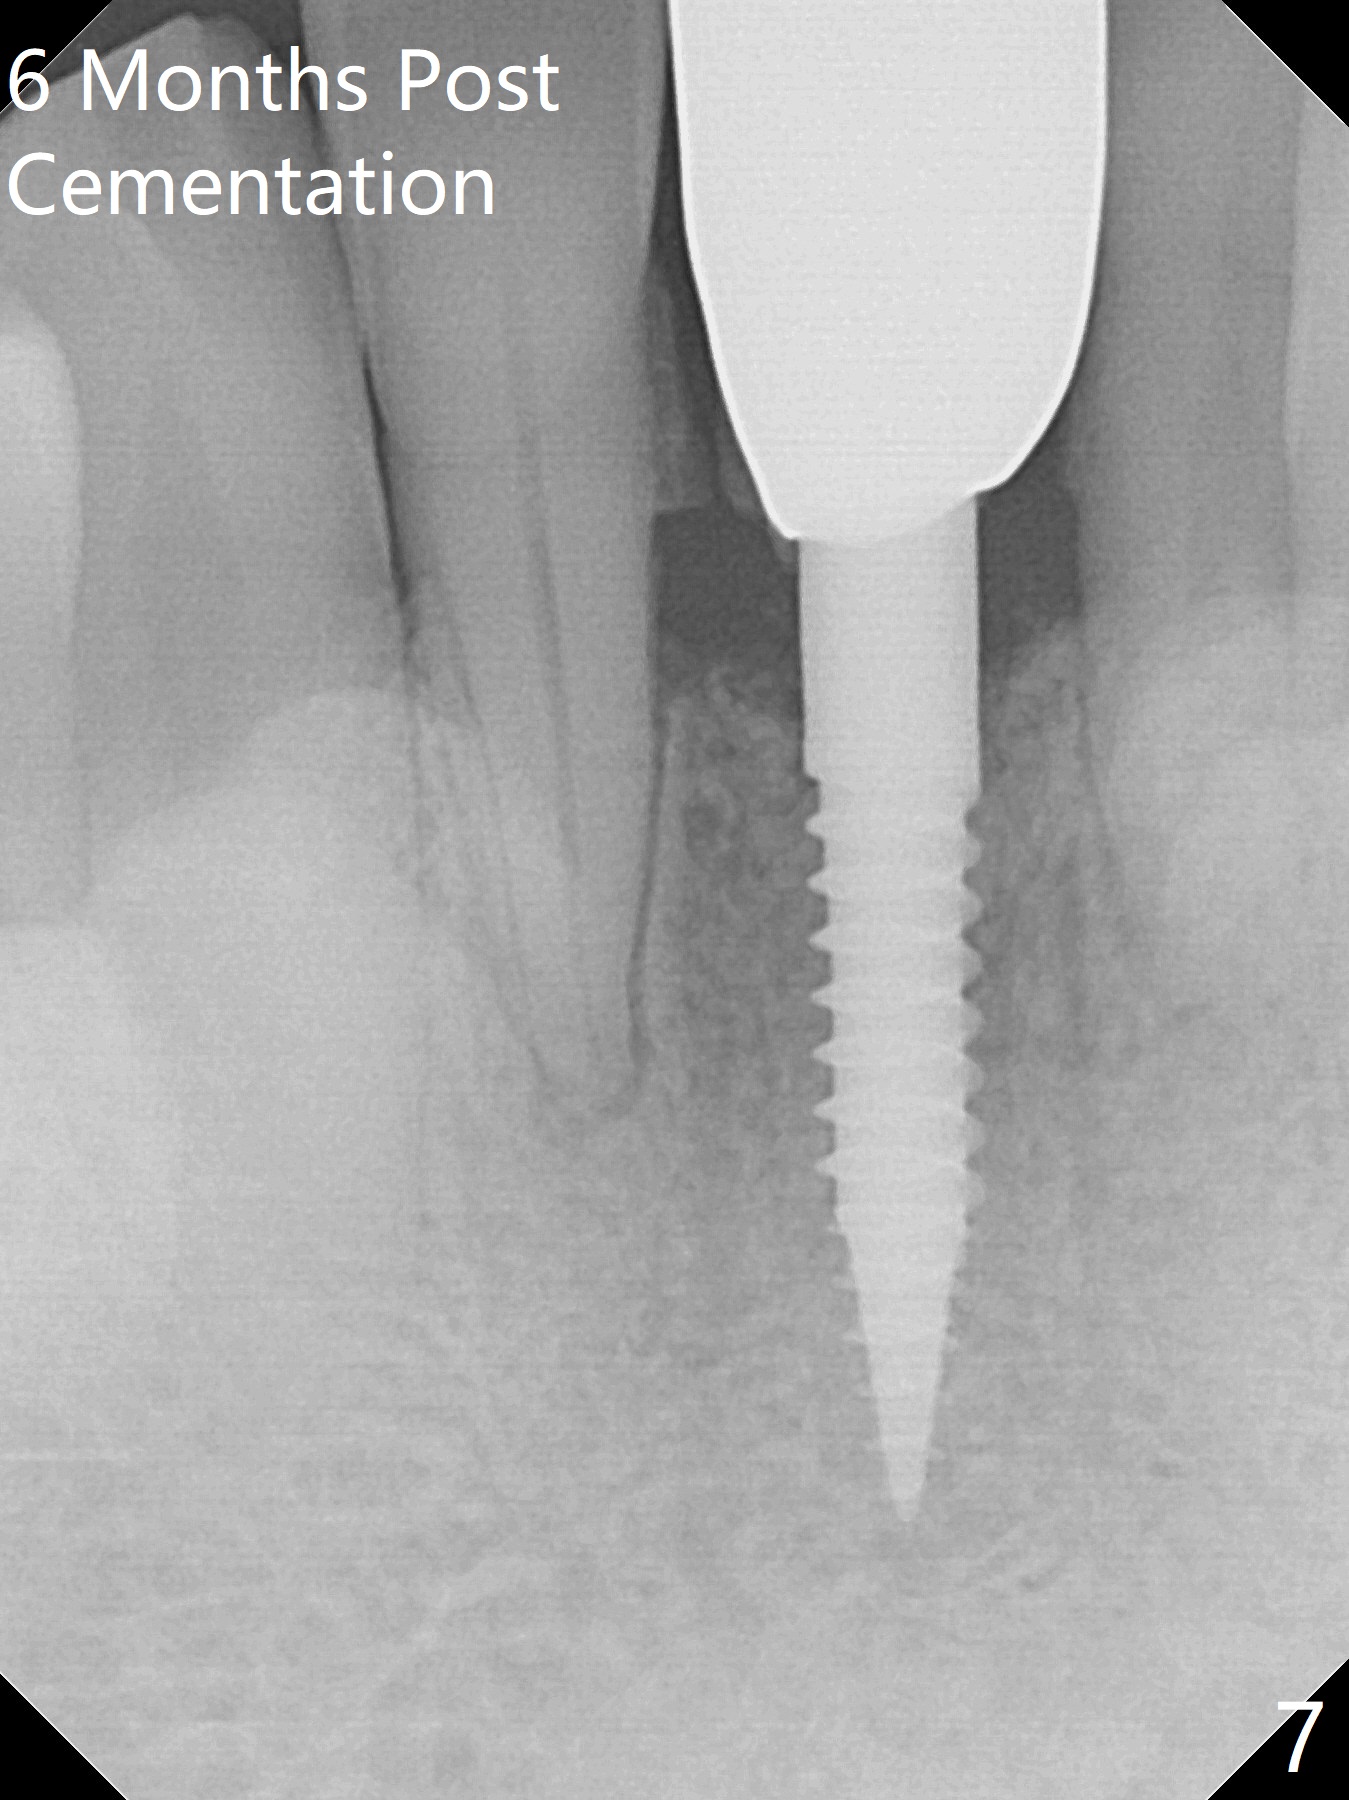

When the patient returns for implant placement 1.5 years after the last treatment (SRP), the tooth #25 has exfoliated, whereas the tooth #24 is severely displaced (Fig.1-3). In fact the buccolingual plates are found to be lost after extraction, corresponding to change in gingival color indicated by an arrowhead in Fig.1. Initial osteotomy with 1.2 mm drill is parallel to the terminal branches of the Incisive Canal (Fig.4 arrowheads). Since the gingiva is as thick as 7.5 mm (Fig.3 arrow), a 3x14 mm 1-piece implant with 4 mm cuff is placed (Fig.5); three implant threads are outside the native bone; with allograft (*) placed and the neighboring crests being coronal to the threads, the chance of periimplantitis should be remote. An immediate provisional is fabricated to contain the graft in place. Meanwhile the tooth #2 is symptomatic with crack. The top 3 threads appear to be contacted by the newly formed crestal bone 6 months postop (Fig.6 *). Bone appears to have grown into the space between implant threads 6 months post cementation (13 months postop).